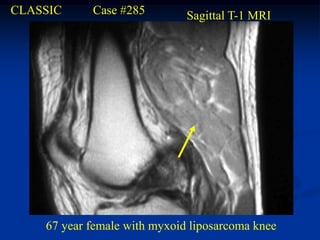

CLASSIC     Case #285         Sagittal T-1 MRI

67 year female with myxoid liposarcoma knee

Myxoid Liposarcoma The myxoid variant is the most common variant of the lipo- sarcoma and it is seen in a slightly younger age group between 40 and 50 years of age. It occurs in the lower extremities in 75% of cases, especially in the popliteal area. These lesions are slow growing and frequently asymptomatic in the early stages. On imaging studies, the MRI is the best method for visualizing these tumors that will have a mixed high and low signal on the T-1 weighted image because of the high percentage of fatty tissue in the tumor. Histologically, there will be evidence of malignant lipoblasts and it is common to find a plexiform network of small capillary tubes running thru the fatty tumor, similar to the capillary hemangioma. The prognosis for this variant is quite good after a wide local surgical resection, followed in most cases by local radiation therapy. The chance of pulmonary metastases runs as high as 20% and occasionally there will be multifocal myxoid

liposarcomas occurring inthe extremities as well as in retro- peritoneal locations. Occasionally, one will see a transitional form of myxoid converting into a higher grade round cell lipo- sarcoma which carries a more guarded prognosis.

CLASSIC Case #285 Sagittal T-1 MRI 67 year female with myxoid liposarcoma knee